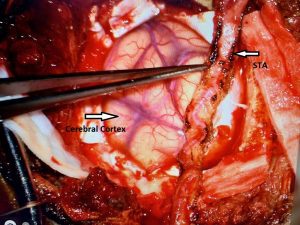

Noninvasive vascular imaging was sufficiently suggestive to warrant conventional digital subtraction angiography, performed by Dr. Brisman and confirming Moya-Moya syndrome (Figures 1). CT Perfusion (Figure 2) showed a decreased transit time of blood to the right hemisphere and the patient was recommended to undergo cerebral revascularization to avert stroke.